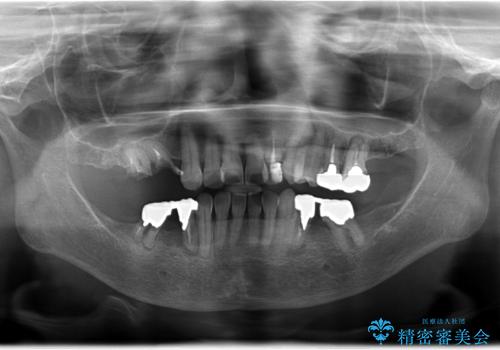

- 奥歯がとれてしまい、咬めないとのことで来院されました。

右上のかぶせ物がとれてしまい、残った根っこも虫歯になってしまっていました。

また右下の歯も虫歯と歯周病により長く使用するには難しい状態でした。

右の上下の歯を抜歯してインプラントを埋入して、かぶせ物を装着する計画としました。